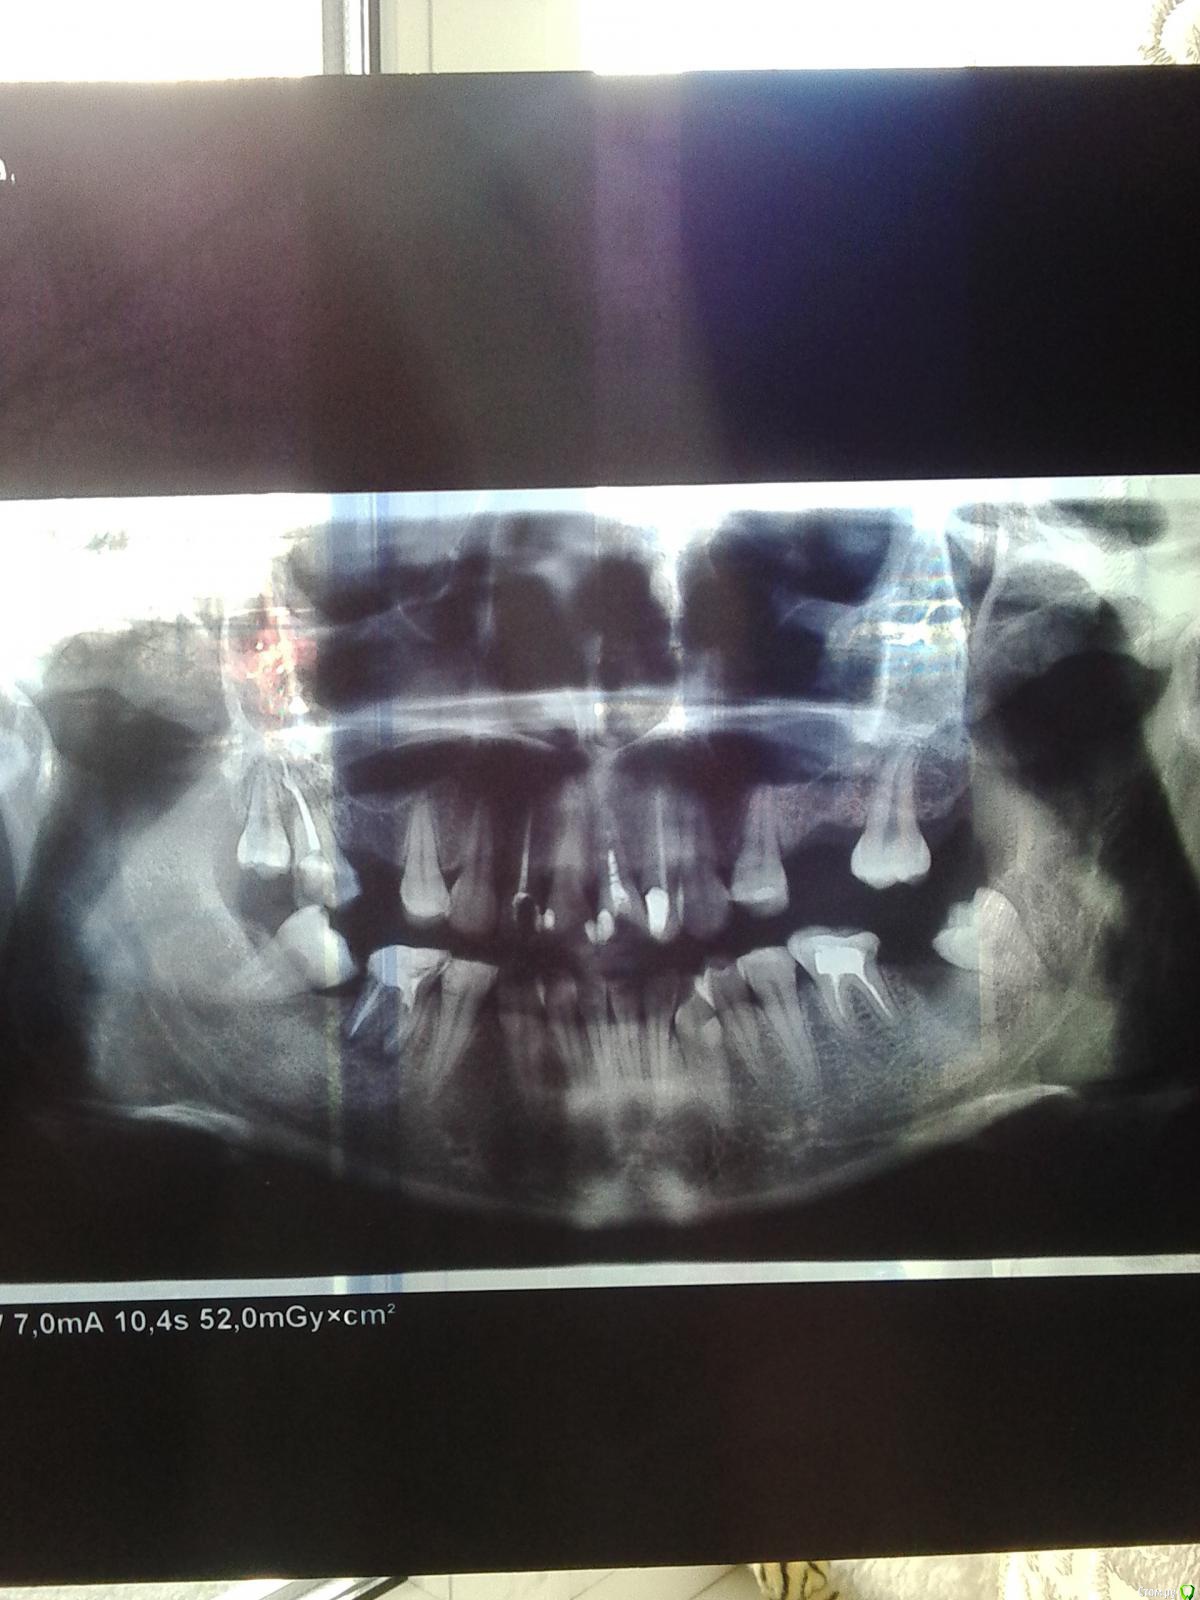

кристина1877 Опубликовано 11 апреля, 2015 Поделиться Опубликовано 11 апреля, 2015 (изменено) Добрый день! Скажите пожалуйста, какой у меня прикус, дистальный или глубокий? (22года) Можно ли в моем случае обойтись без хирургического вмешательства и исправить прикус только брекет-системой. Не нравится как верхняя губа выступает над нижней..смотрится некрасиво.. Ортодонт, у которого планирую лечиться предлагает многопетлевую технику. Прилагаю фото Добрый день! Скажите пожалуйста, какой у меня прикус, дистальный или глубокий? (22года) Можно ли в моем случае обойтись без хирургического вмешательства и исправить прикус только брекет-системой. Не нравится как верхняя губа выступает над нижней..смотрится некрасиво.. Ортодонт, у которого планирую лечиться предлагает многопетлевую технику. Прилагаю фото Изменено 11 апреля, 2015 пользователем кристина1877 Ссылка на комментарий

Yana guapa Опубликовано 12 апреля, 2015 Поделиться Опубликовано 12 апреля, 2015 Добрый день! Скажите пожалуйста, какой у меня прикус, дистальный или глубокий? (22года) Можно ли в моем случае обойтись без хирургического вмешательства и исправить прикус только брекет-системой. Не нравится как верхняя губа выступает над нижней..смотрится некрасиво.. Ортодонт, у которого планирую лечиться предлагает многопетлевую технику. Прилагаю фото Кристина, прикус может быть одновременно и дистальным и глубоким. Точно диагноз ставится и план лечения составляется после расчета ТРГ (на вашем фото - снимок нечитаемый). Плюс у Вас множественные дефекты зубных рядов, смещения... Суть не в том как обозвать прикус и какой техникой лечить, а суть в том - что Именно Вы и Ваш врач планируете получить на выходе и каким способом. Ссылка на комментарий

кристина1877 Опубликовано 12 июня, 2015 Автор Поделиться Опубликовано 12 июня, 2015 Кристина, прикус может быть одновременно и дистальным и глубоким. Точно диагноз ставится и план лечения составляется после расчета ТРГ (на вашем фото - снимок нечитаемый). Плюс у Вас множественные дефекты зубных рядов, смещения... Суть не в том как обозвать прикус и какой техникой лечить, а суть в том - что Именно Вы и Ваш врач планируете получить на выходе и каким способом. Посмотрите пожалуйста ТРГ, как думаете, можно ли обойтись без остеотомии? Ссылка на комментарий